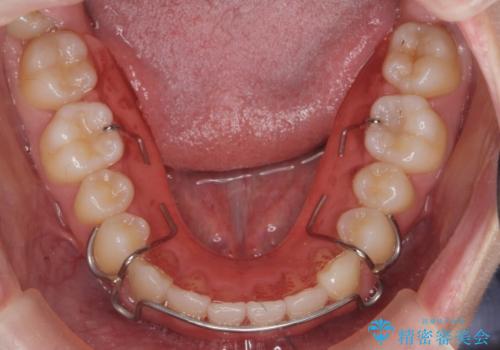

ガタつきの改善 マウスピース矯正治療

- 歯のがたつきの改善を求めて、矯正治療を希望され来院されました。

少量の歯のディスキング、歯列弓拡大、アタッチメントを装着することで審美的な歯列へとマウスピース矯正インビザラインを用いて治療を行います。

マウスピース矯正は装着時間の遵守が非常に大切ですが、しっかりと20時間/日以上の装着を守っていただいたおかげで良好な治療結果を得ることができました。

- 矯正治療後の保定が不十分だと後戻り(元の位置に戻ろうとする動き)をします